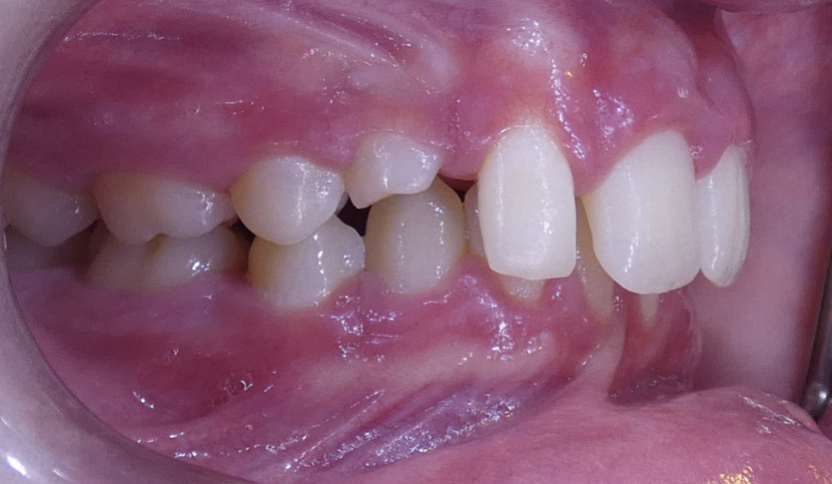

Posterior Crossbite

Top teeth are inside of bottom teeth.